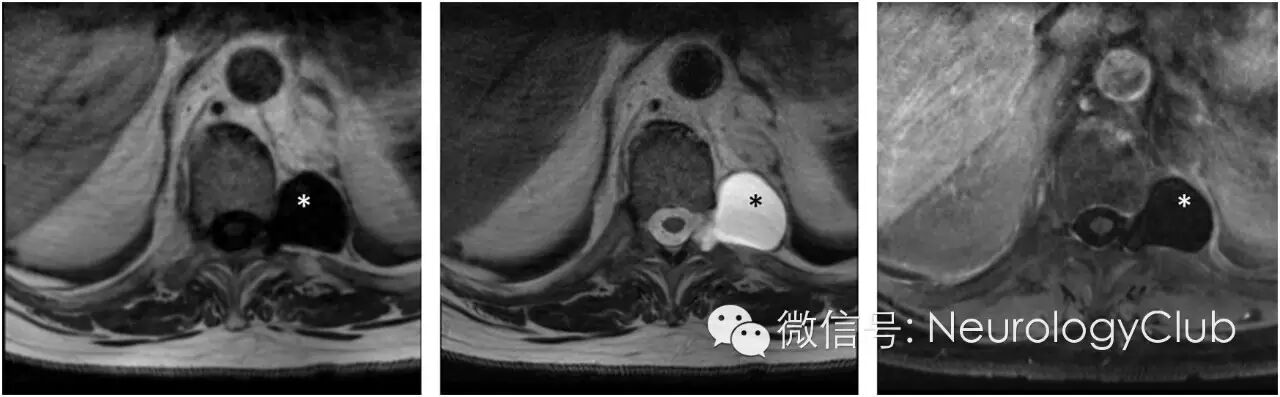

54岁男性,因一次晕厥发作被送至急诊室,初步检查后认为是继发于心脏原因。患者既往有高血压,高脂血症和酗酒史。无头痛,视物模糊,运动无力,感觉缺失或背痛。神经系统查体无殊。患者胸部X片见可疑肺部肿块,再行CT检查,提示源自T10神经孔的均匀低密度脊柱肿块伴小孔增宽。脊髓MRI进一步证实左侧T10-11椎间孔处3.6×3.7×2.5cm囊性病灶,延伸至椎旁软组织(图1)。类似1.5cm的囊性变还位于T3-T4神经孔,此外多个水平椎间孔可见多发小囊肿(图2)。

(图1:T1WI[左],T2WI[中]以及增强压脂MRI[右]可见一边界清楚哑铃型病灶[*],大小约3.6×3.7cm,无边缘强化,位于左侧T10-T11椎间孔,导致孔增宽)

(图2:矢状位T2WI[左和中]可见T10-11和T3-4水平高信号病灶[箭],提示病变多灶性本质,横断面T2WI[右]上可见T3-T4水平右侧病灶[*]显示更清楚)